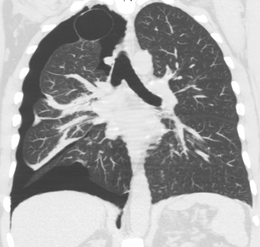

Computed tomography

Computed tomography (CT, or "CAT scan") is not necessary for the diagnosis of pneumothorax, but it can be useful in particular situations. In some lung diseases, especially emphysema, it is possible for abnormal lung areas such as bullae (large air-filled sacs) to have the same appearance as a pneumothorax on chest X-ray, and it may not be safe to apply any treatment before the distinction is made and before the exact location and size of the pneumothorax is determined.[13] In trauma, where it may not be possible to perform an upright film, chest radiography may miss up to a third of pneumothoraces, while CT remains very sensitive.[16]

A further use of CT is in the identification of underlying lung lesions. In presumed primary pneumothorax, it may help to identify blebs or cystic lesions (in anticipation of treatment, see below), and in secondary pneumothorax it can help to identify most of the causes listed above.[13][17]